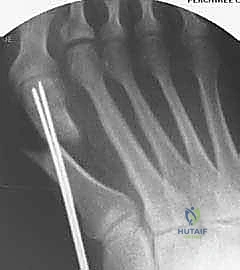

الصورة توضح مفهوم "التصحيح المثالي" لورم إبهام القدم، حيث يتم رسم خط موازٍ للعظم المشطي الثاني يلامس قاعدة العظم المشطي الأول. يساعد هذا التخطيط الدقيق الأستاذ الدكتور محمد هطيف في تحديد مكان ودرجة التحريك اللازمة للعظم المشطي بدقة متناهية.

الدقة هي مفتاح النجاح. يوضح هذا التخطيط كيف يقوم الدكتور هطيف بحساب زوايا القص العظمي بالملليمتر قبل بدء الجراحة لضمان استعادة الميكانيكا الحيوية السليمة للقدم.

إدخال أسلاك التوجيه (K-wires) لتثبيت العظم مؤقتاً والتأكد من الوضعية الصحيحة باستخدام جهاز الأشعة السينية داخل غرفة العمليات (C-arm) قبل وضع المسامير النهائية.